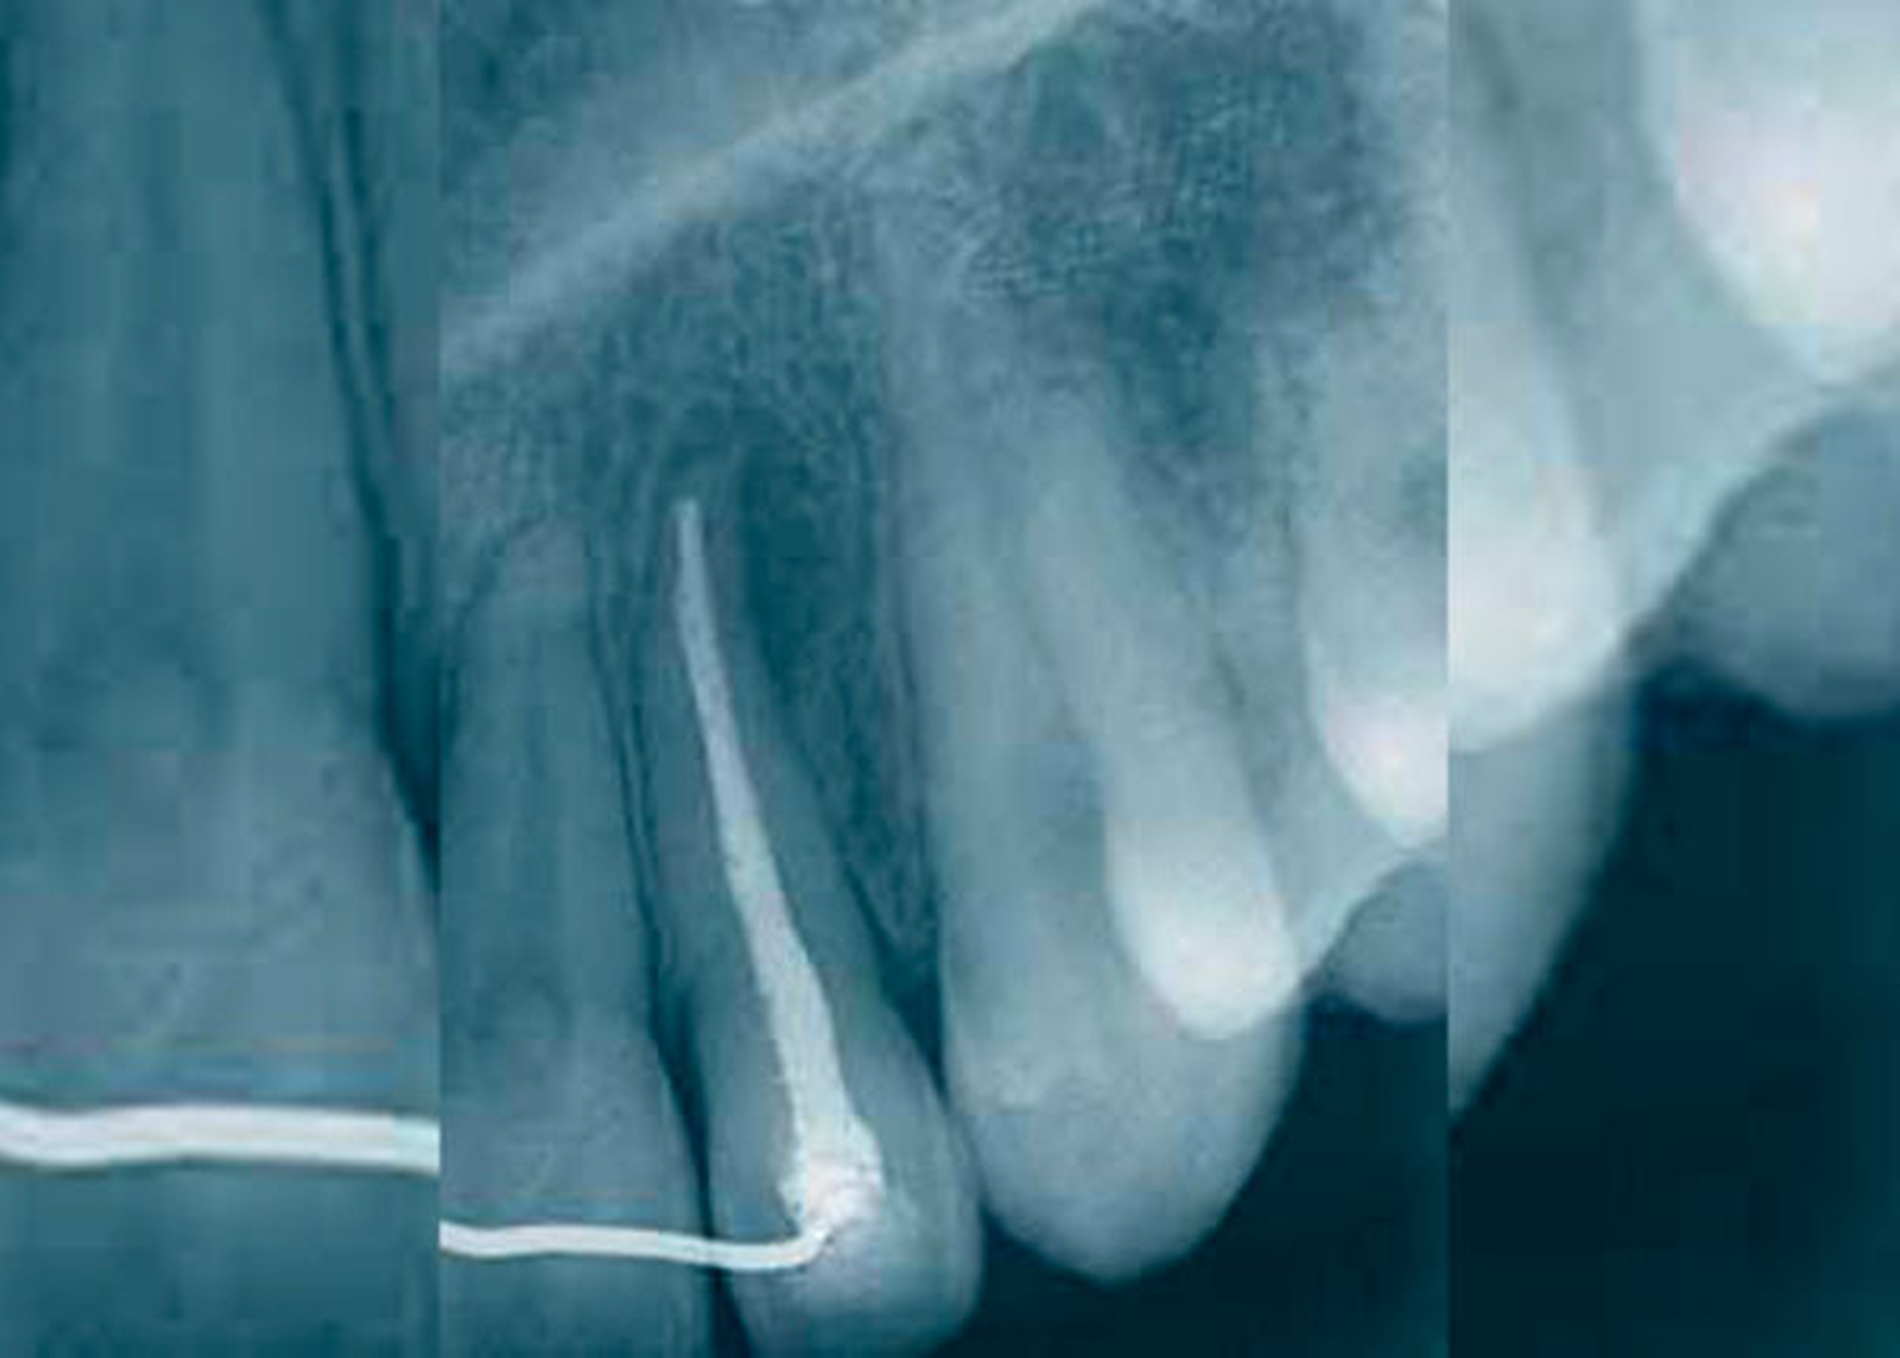

Die GZ wurde auch der parodontalen Zyste gegenübergestellt. Während letztere zwischen den Wurzeln sämtlicher Zähne entstehen kann, erscheint die GZ typischerweise nur zwischen dem lateralen Schneidezahn und dem Eckzahn, dort wo sich Prämaxilla und Maxilla vereinen. Es wurde Wert darauf gelegt, dass die Zyste zwischen parodontal und pulpal gesunden Zähnen vorkommt und somit ein Zweifel an ihrem fissuralen Ursprung ausgeschlossen ist. Die GZ verdrängt die Wurzeln des lateralen Incisivus und des Eckzahns, was als erstes klinisches Zeichen beschrieben wird. Später kann es zu einer Vorwölbung der vestibulären Schleimhaut kommen, oft assoziiert mit einem Druckgefühl (Abb. 1 bis 5).

Die klinische und pathohistologische Evidenz spricht überzeugend dafür, dass Zysten im „Globulomaxillären Bereich“ radikuläre Zysten, laterale Parodontalzysten, odontogene Keratozysten [Christ, 1970], kalzifizierende odontogene Zysten, adenomatoide odontogene Tumore [Rosenberg & Cruz, 1963; Giansanti et al., 1970; Khan et al., 1977], odontogene Myxome [Rud, 1964; Taicher & Azaz, 1977], Ameloblastome [Aisenberg & Inman, 1960], zentrale Riesenzellgranulome oder hämorrhagische Knochenzysten [Peters & Wassow, 1968] sind (Abb. 6 bis 13).

Auch die Möglichkeiten von invaginierten Zähne [Galindo-Moreno et al., 2003] oder von apikalen Infektionen, die beim Foramen caecum oberer lateraler Inzisivi ihren Ursprung genommen haben, sollten in die Differentialdiagnose miteinbezogen werden. Zahninvaginationen kommunizieren häufig mit der Pulpa, was früher oder später zur Pulpanekrose und zur Parodontitis apicalis führen und eine GZ vortäuschen kann [Galindo-Moreno et al., 2003]. Eine Entstehungstheorie aus einer verkümmerten Zahnanlage im „Globulomaxillären Bereich“ klingt zwar verlockend, wurde aber in der Literatur bis heute nicht ausreichend untersucht.